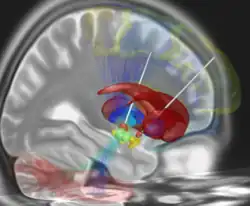

- Die Anwendung der tiefen Hirnstimulation bei der Depression befindet sich im experimentellen Stadium.[5][6] Positive Resultate konnten bei sehr kleinen Gruppen von therapieresistenten Patienten bei einer Stimulation der Area subgenualis[7] (Feld 25. Brodmanns) und des Nucleus accumbens[8][9] gezeigt werden. Thomas Schläpfer und Volker A. Coenen erzielten gute Ergebnisse durch Positionierung der Elektrode an dem Nervenstrang, der den tief liegenden Hirnstamm zur stirnseitigen Hirnrinde mit den Strukturen Area subgenualis und Nucleus accumbens verbindet.[10][11]

Bei der Behandlung von Patienten mit fortgeschrittener Parkinson-Krankheit wird der Nucleus subthalamicus angesteuert oder der mediale Globus pallidus, bei essentiellem Tremor der Thalamus ventralis und bei Dystonie der Globus pallidus. Eine Studie der Universitätskliniken Köln und Bonn zur Wirksamkeit bei Depression untersucht die Stimulation des Nucleus accumbens.[15][17]